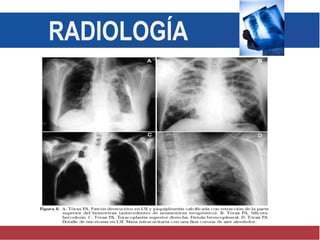

Radiología

Patrón pleural Patrón

traqueobronquial.